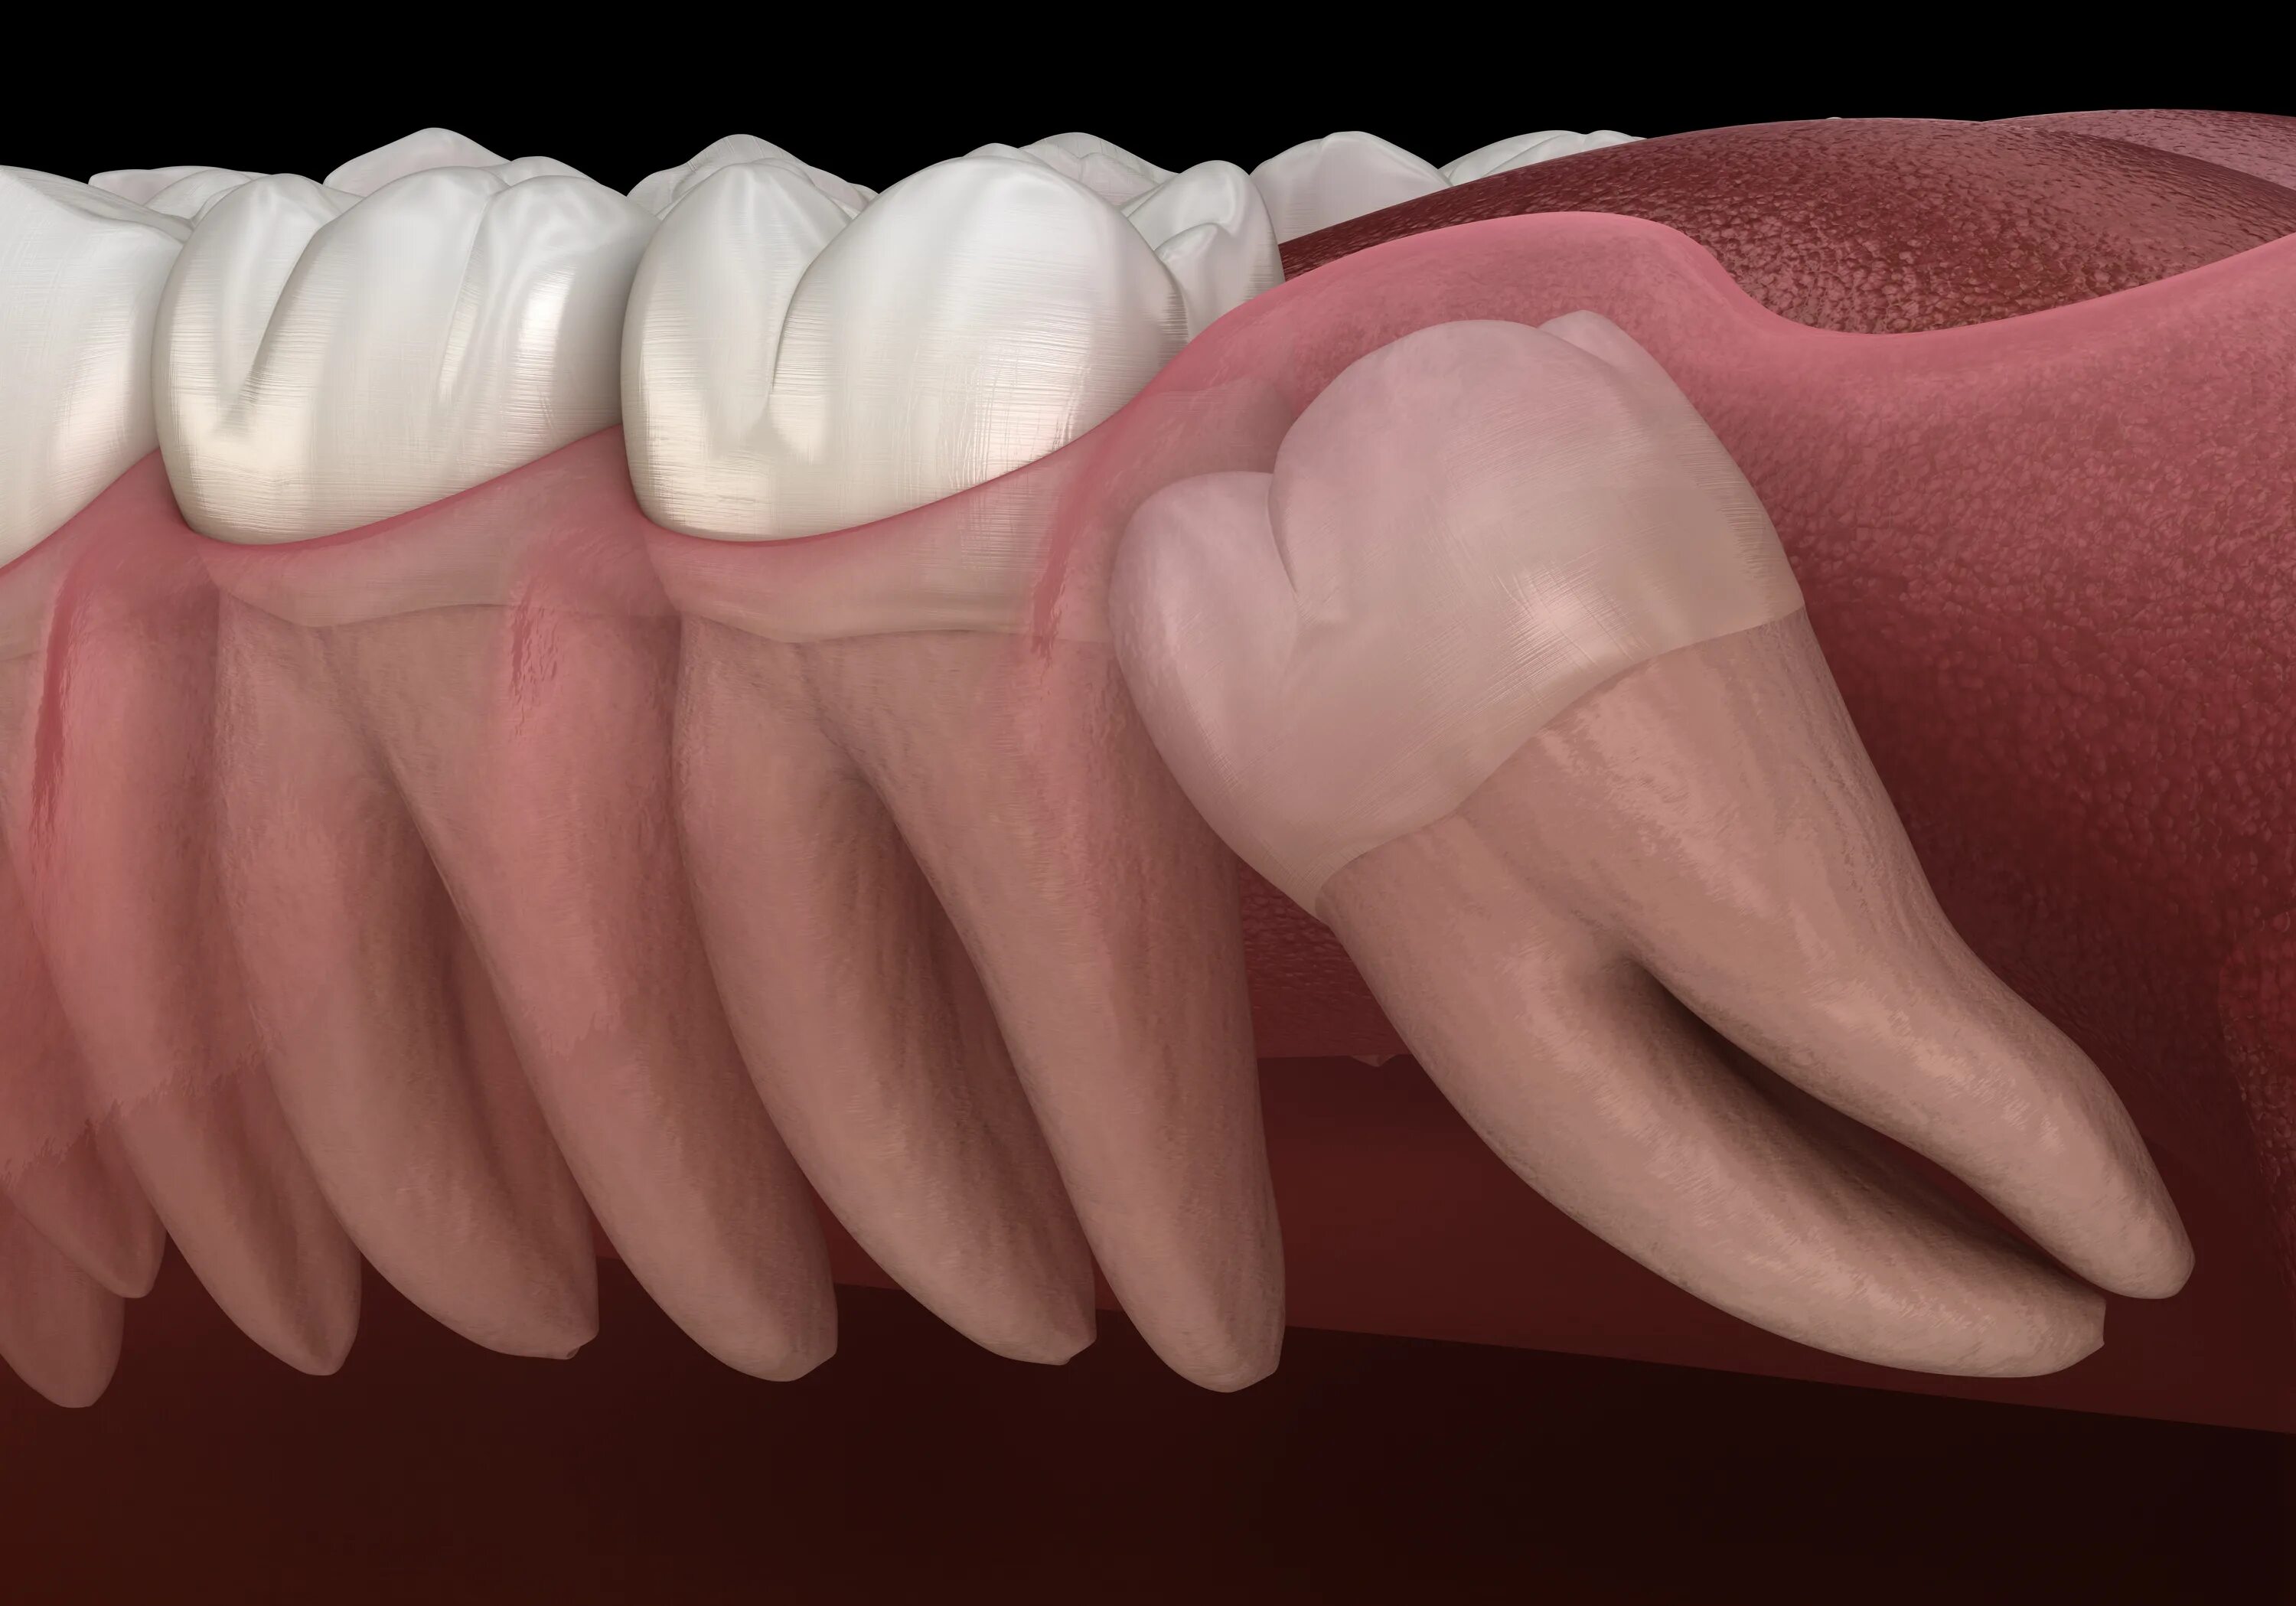

Удаленный зуб 8